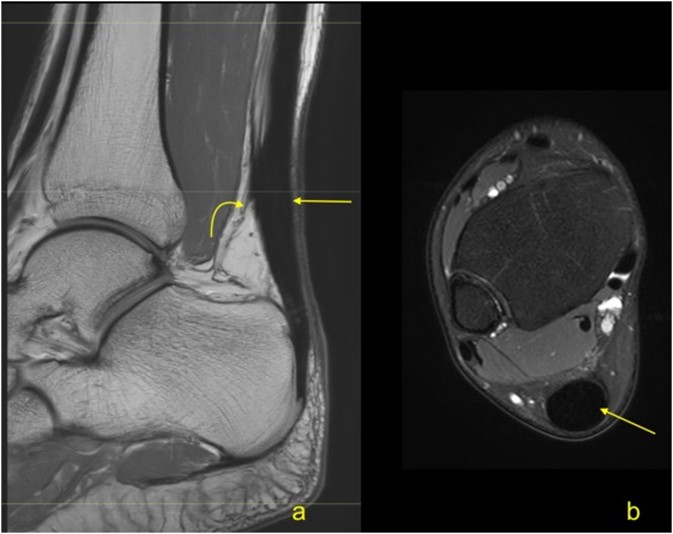

Η διάγνωση τίθεται κλινικά από τον Ορθοπαιδικό με βάση τα συμπτώματα, το ιστορικό και την κλινική εξέταση. Απεικονιστικά θα επιβεβαιωθεί με τη μαγνητική τομογραφία στην οποία θα φανούν τα χαρακτηριστικά ευρήματα της τενοντοπάθειας.